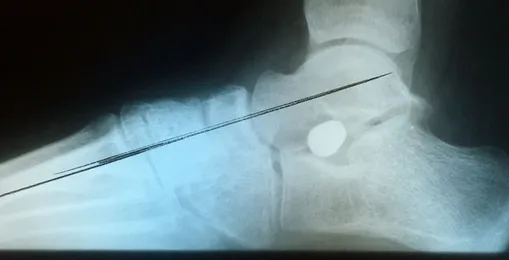

Pre and Postop X-rays Subtalar Joint Implant (Below)

Patient JD

Pre and Postop Subtalar Implant and Percutaneous Achilles Lengthening Below. The first pics show wedging of the distal tibia physis causing ankle valgus due to constant pressure caused by the severity of the flatfoot (JT)